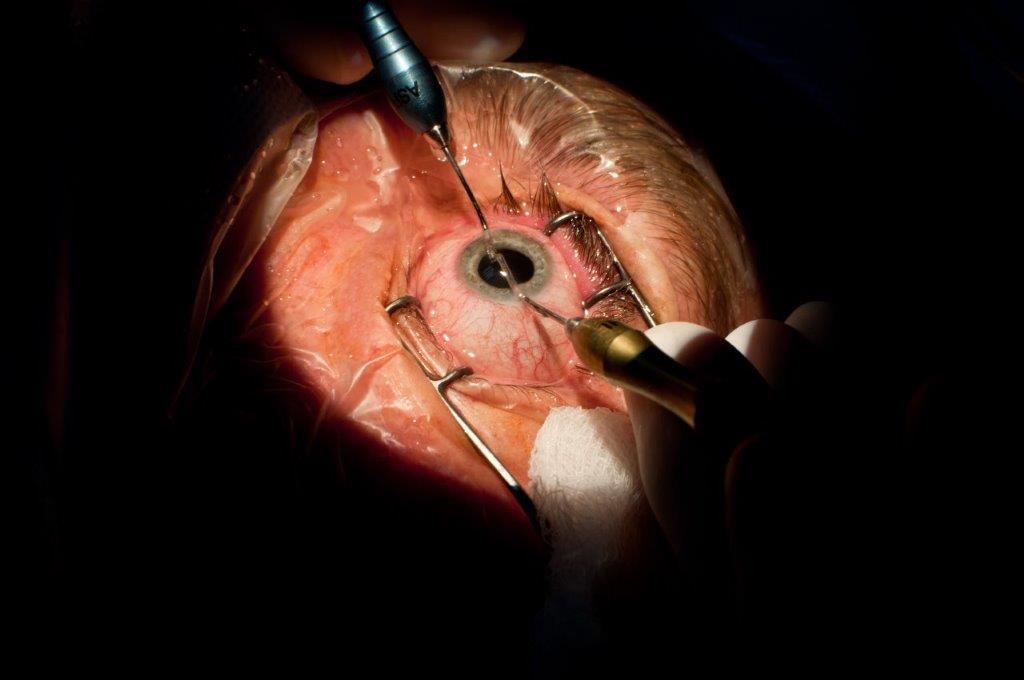

Trauma

Angle recession can result from severe blunt trauma in which a tear occurs in the face of the ciliary body, usually between the longitudinal and circular muscle. Tears can occur over a limited area or may involve the entire angle. If greater than two thirds of the angle is involved, there is a 10% risk of developing glaucoma months or even years after the injury. Gonioscopic examination shows a wide ciliary body band and the ciliary face may appear lighter in the recessed area because there is little ciliary tissue overlying the sclera. If a linear defect is seen at the ciliary body face, a cyclodialysis cleft should be suspected6. It is useful to compare eyes to determine if the ciliary body band appears abnormally wide in one eye (Fig 3).

Fig 3: Angle recession (arrow) demonstrated in the angle post blunt trauma